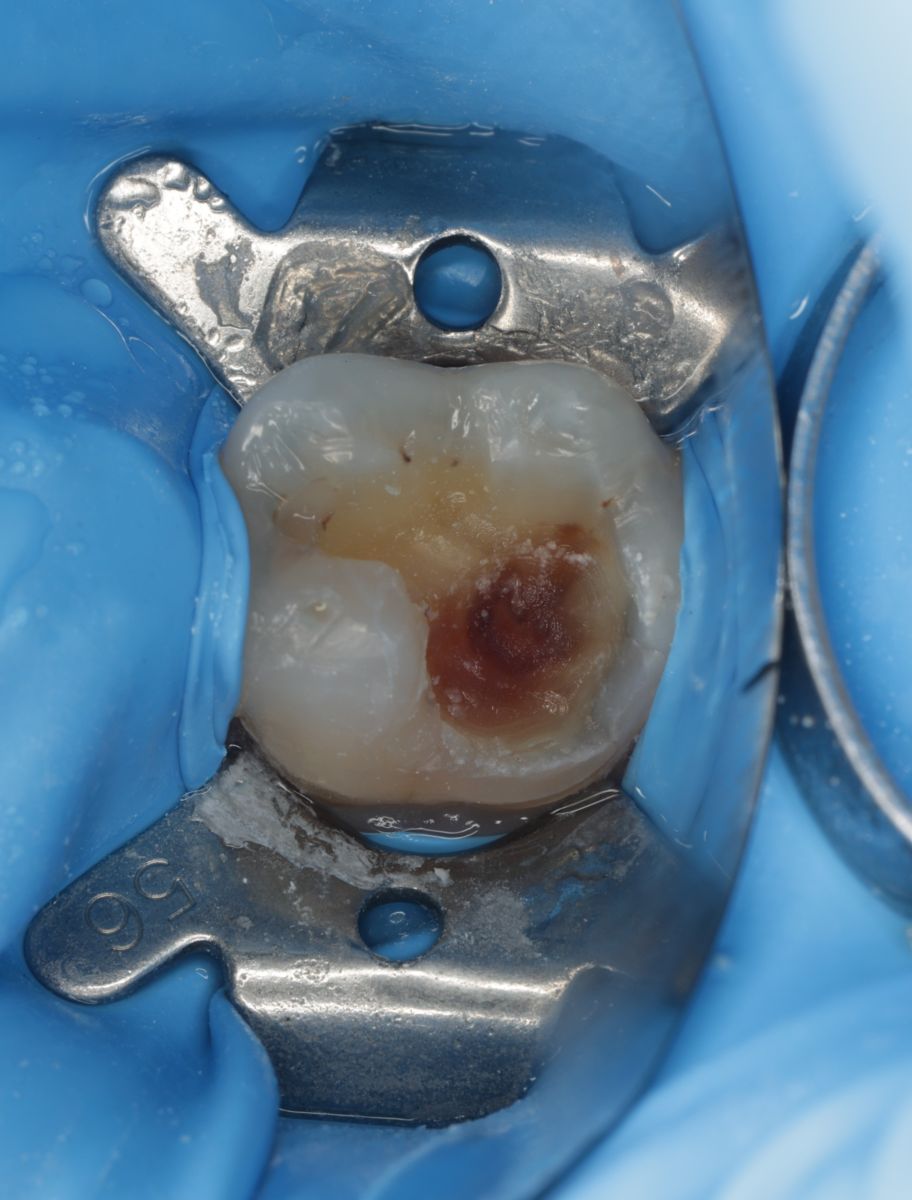

【 案 例 三】

- 有時候表面上看起來是蛀牙是一個小缺口,其實裡面已經是範圍很大的蛀牙了!用隔濕的小帳棚隔絕汙染、清理蛀牙,缺損的齒質就靠陶瓷齒雕(瓷塊)做修復!仿真的色澤及外觀,讓你看不出來牙齒曾經的損傷。